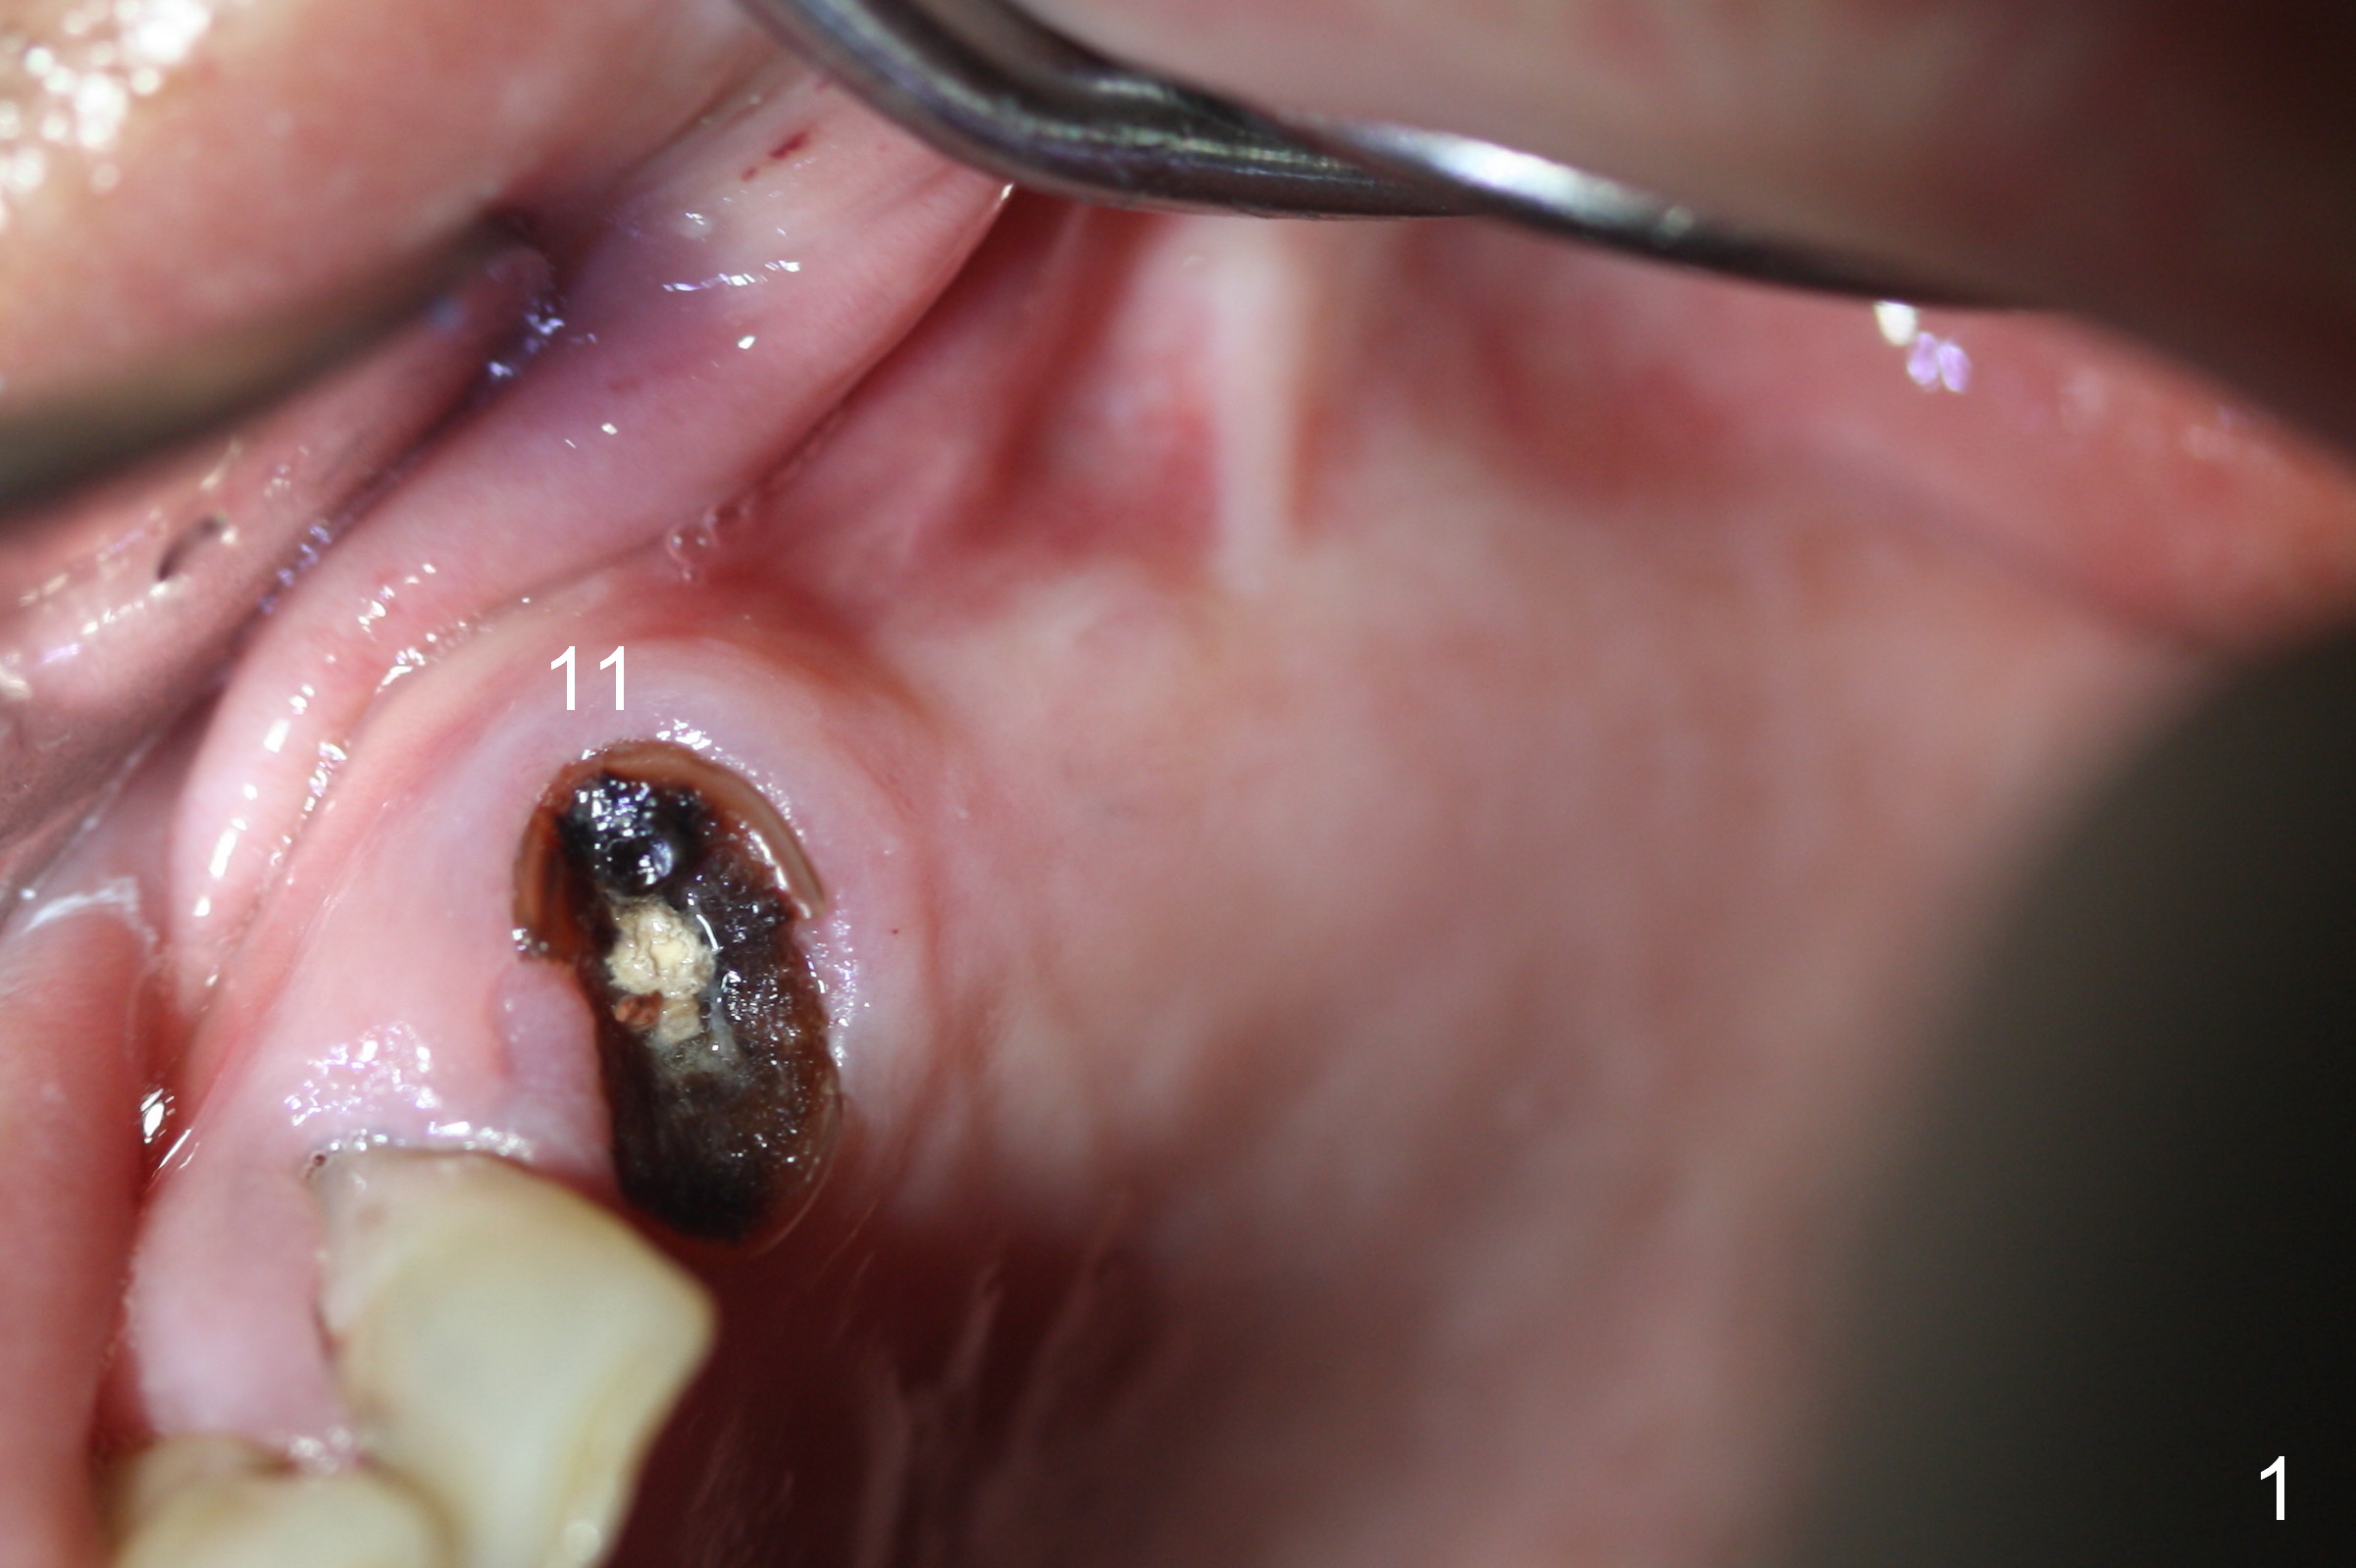

The edentulous ridge distal to #11 residual root is moderately atrophic (Fig.1). The ridge is split with 10 and 13 mm saws between initial osteotomies at #12,14 and 15 (Fig.2). Parallel pins are inserted for trajectory confirmation (Fig.3,4). The gap of the split ridge between #12 and 14 increases when bone expanders (2.7/3.6 mm) are being inserted. A 4.5x17 mm implant does not obtain primary stability at #12. When a 5x17 mm implant is being placed at #12, the buccal plate starts to crack. When the same implant is placed at #14, the crack appears to get larger. Drills are used to finish osteotomy at #14 with force being applied palatally. When the implant is re-inserted, the buccal plate fractures does not appears to get worse (Fig.5 <). In contrast, there is no obvious increase in the gap between #14 and 15 when bone expanders are being used at #15. To avoid complication, drills are used to finish osteotomy before placing a 4.5x14 mm at #15 (Fig.7 (#11: 4.5x17 mm)). CBCT shows that the bone density at #12 and 14 (400-500 Hounsfield units (HU)) is higher than that at #15 (200-300 HU). Ridge split is successful when HU is <200 with smaller diameter implants.